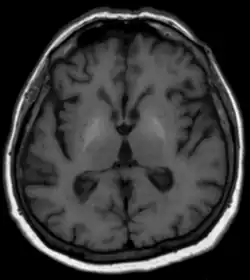

Für die Diagnostik der zugrunde liegenden Lebererkrankung stehen die üblichen Methoden der Blutuntersuchungen, Sonographie und anderer Schnittbildverfahren sowie die Klinik und gegebenenfalls eine Gewebeprobe der Leber mit histologischer Untersuchung zur Verfügung. Bezüglich der Degeneration im Gehirn sind in der Computertomographie meist keine Veränderungen zu erkennen. Die MRT zeigt typischerweise in den Basalganglien in T1-gewichteten nativen Sequenzen eine Signalerhöhung. Als Ursache werden Ablagerungen von paramagnetischen Mineralien vermutet, die nach Lebertransplantation auch reversibel sein können. T2-gewichtete Aufnahmen zeigen meist keine Auffälligkeiten. Differentialdiagnostisch werden die oben beschriebenen Signalveränderungen gelegentlich bei langer parenteraler Ernährung aber auch bei idiopathischen Verkalkungen gesehen. Auch ein Morbus Wilson ist differentialdiagnostisch in Erwägung zu ziehen.